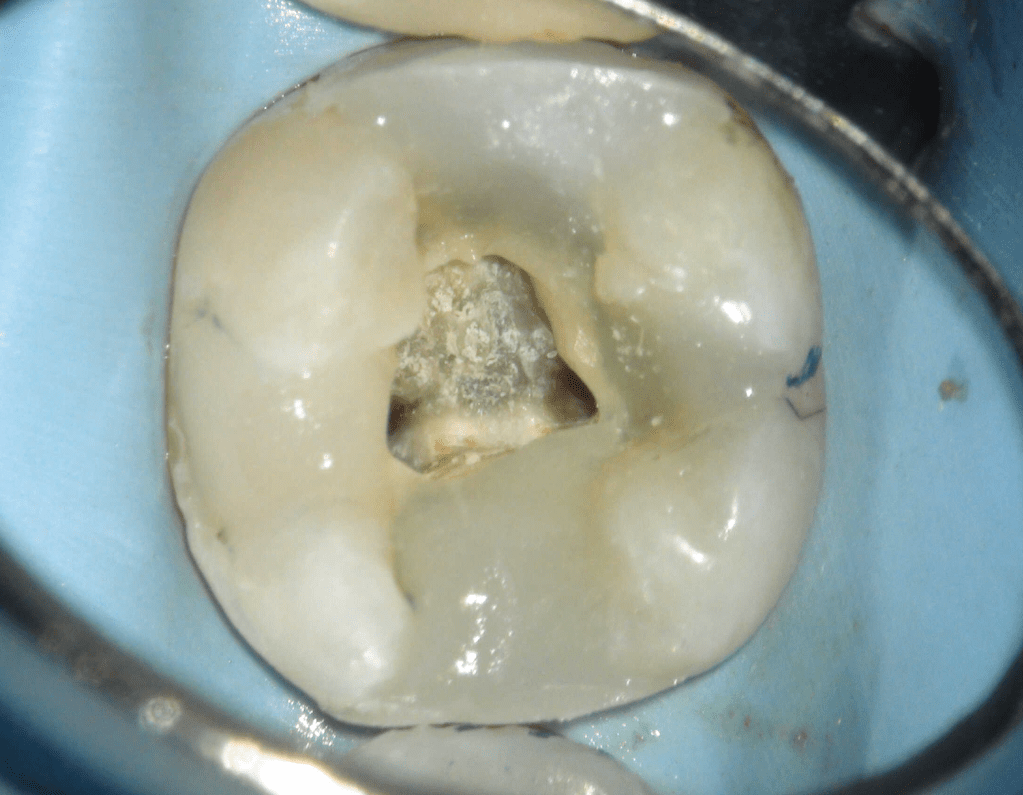

Reco pared vesticular